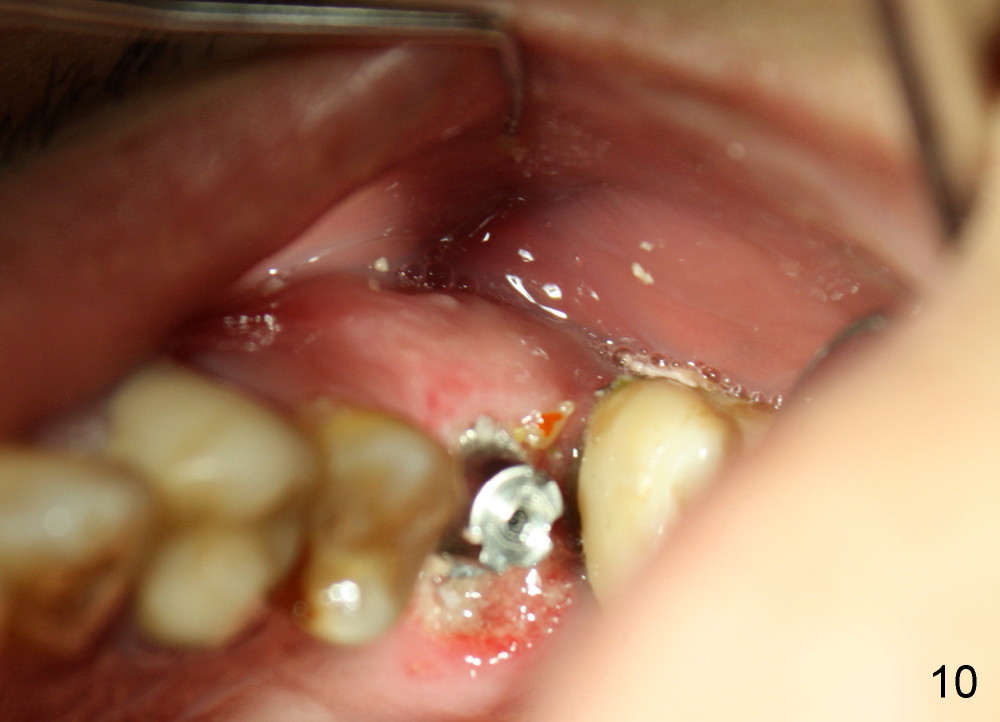

One week later, the lingual portion of the perio dressing is dislodged. The wound is healing, while part of bone graft is exposed (Fig.9 ^). The remaining perio dressing is removed before repacking (Fig.10): it appears that the buccal fistula has disappeared, as compared to preop.